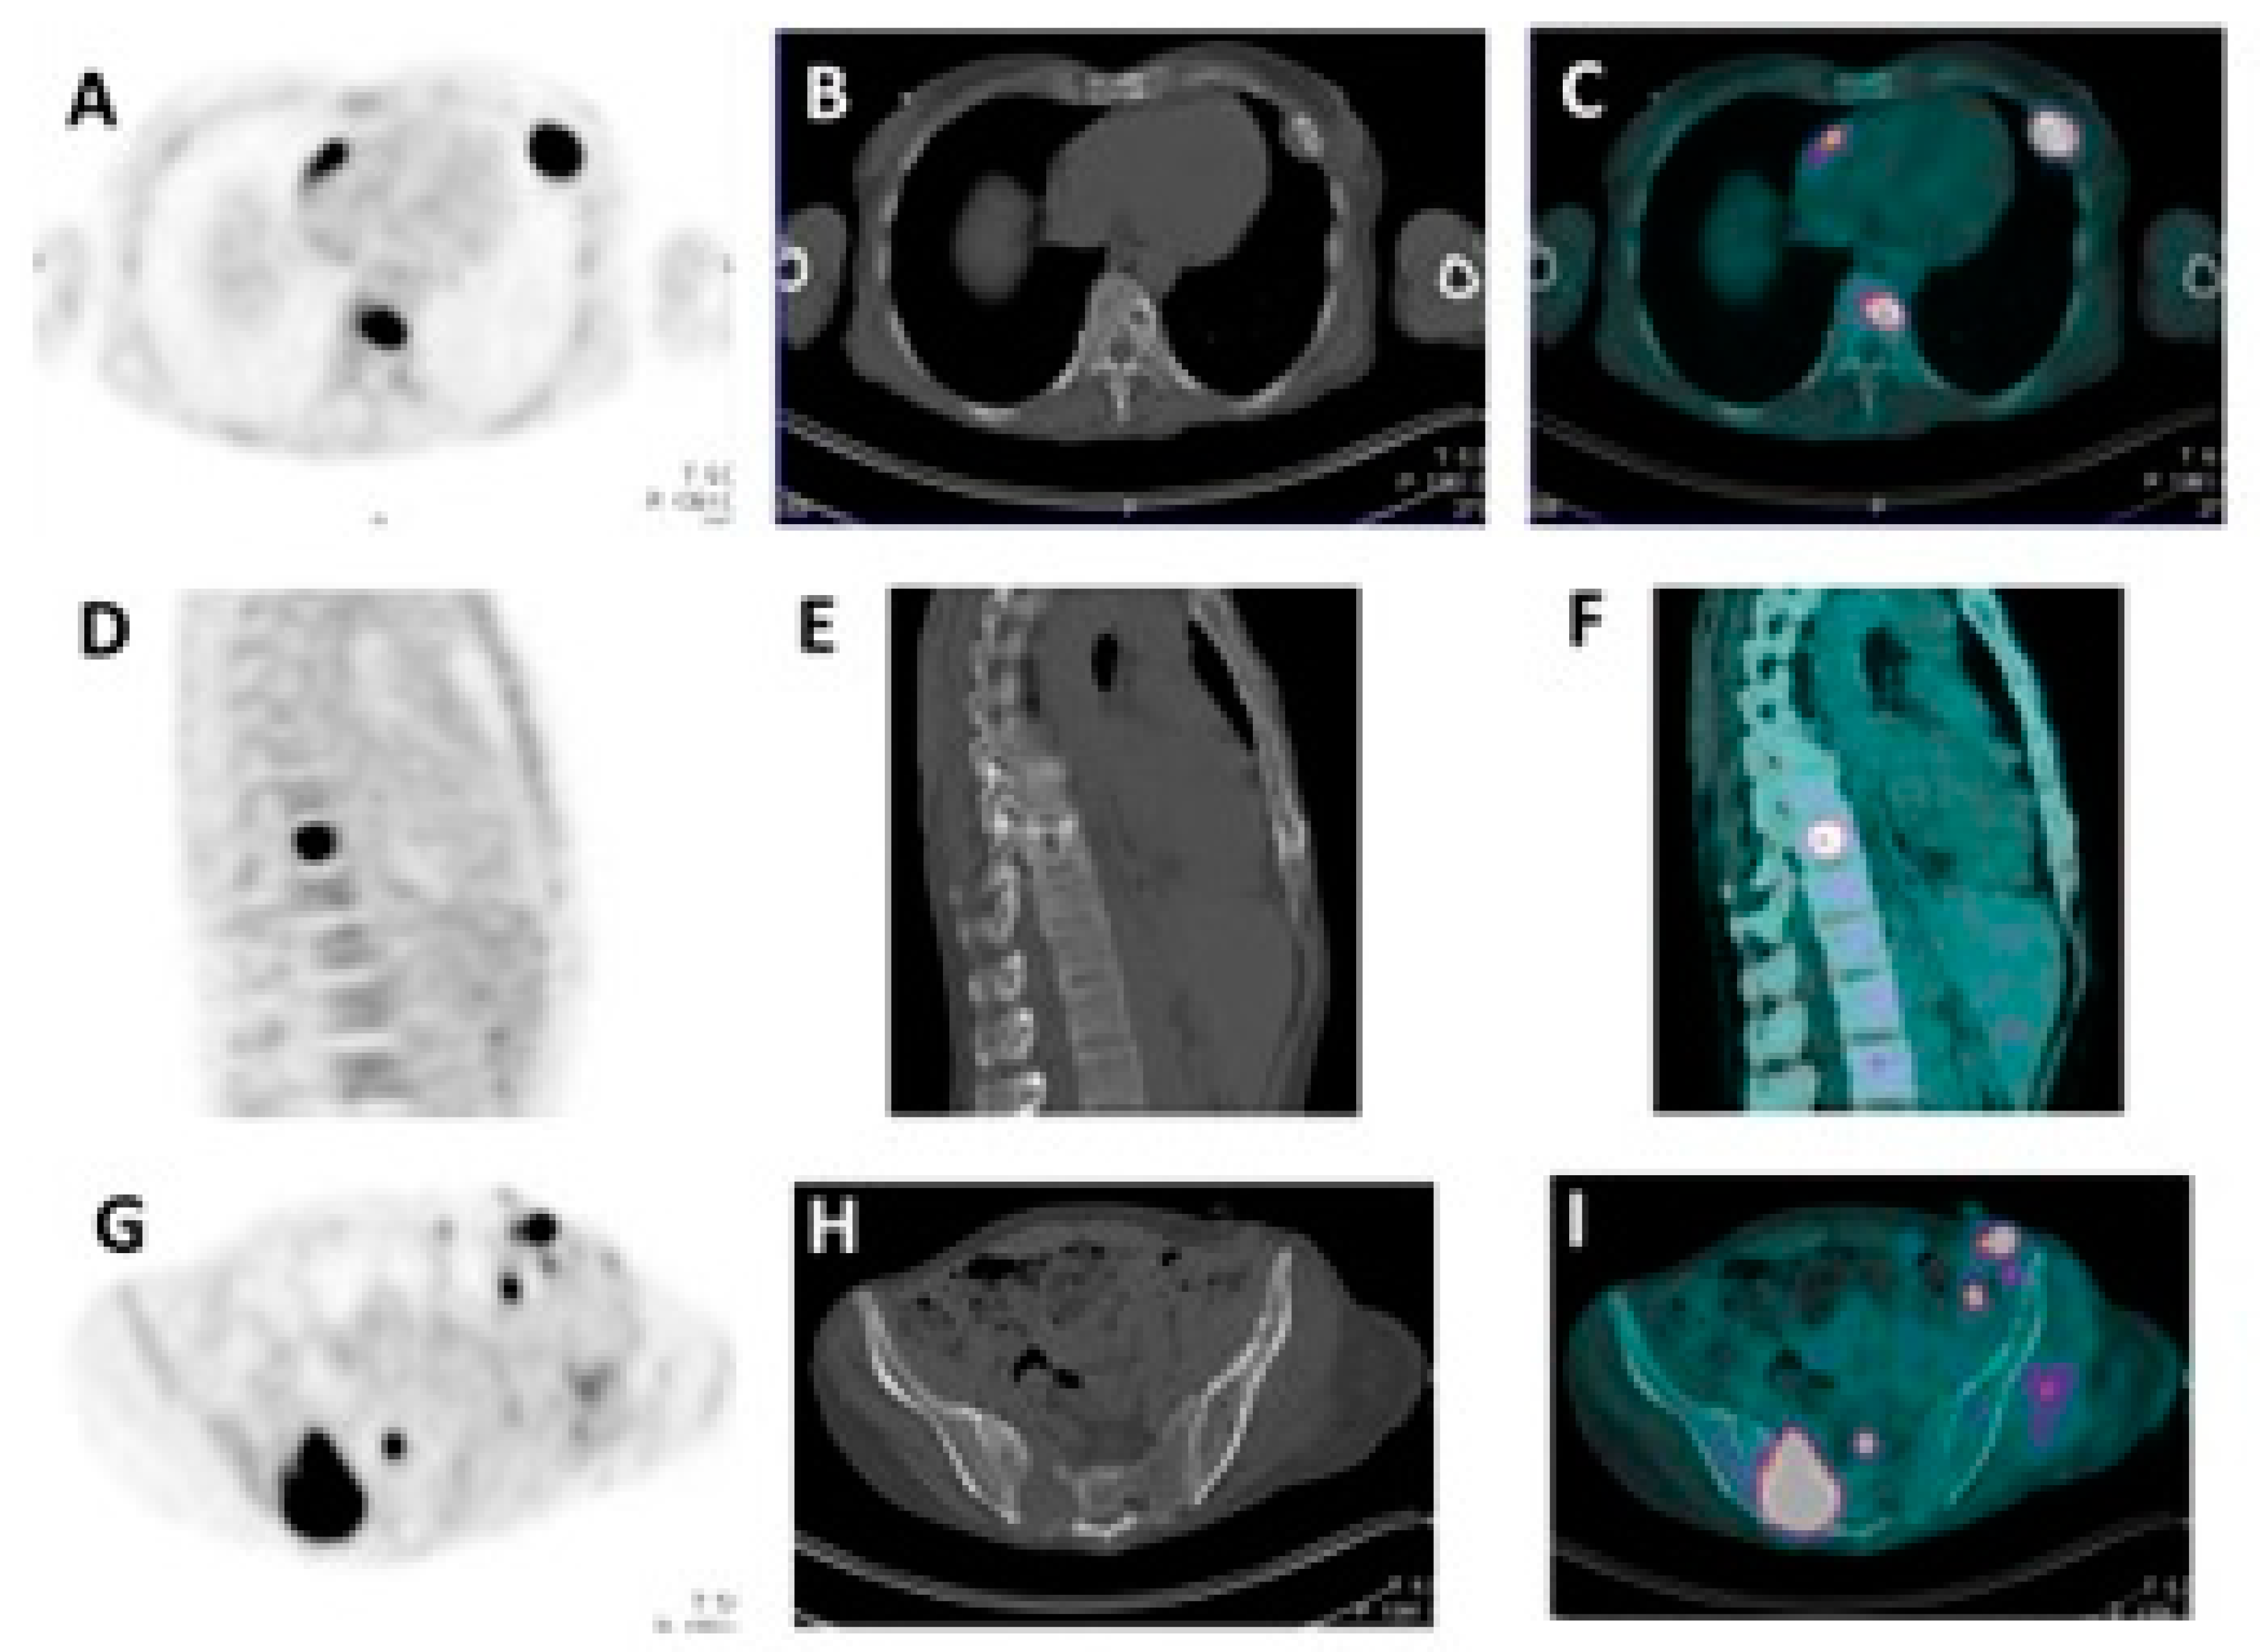

4. FDG PET/CT Images Interpretation in Therapy Monitoring of Multiple Myeloma

5. Diagnostic and Prognostic Value of FDG PET/CT in the Response Assessment in Multiple Myeloma